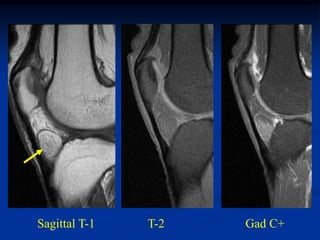

Case #297.2     Hemangioma forearm

46 yr male with

tender soft mass

forearm for years

Cor T-1   T-2   Gad

Sag T-1   T-2   Gad

Axial T-1         T-2

Gad

Case #297.2 Hemangioma forearm 46 yr male with tender soft mass forearm for years

• 310.

• 311.

• 312.

Axial T-1 T-2 Gad

• 313.